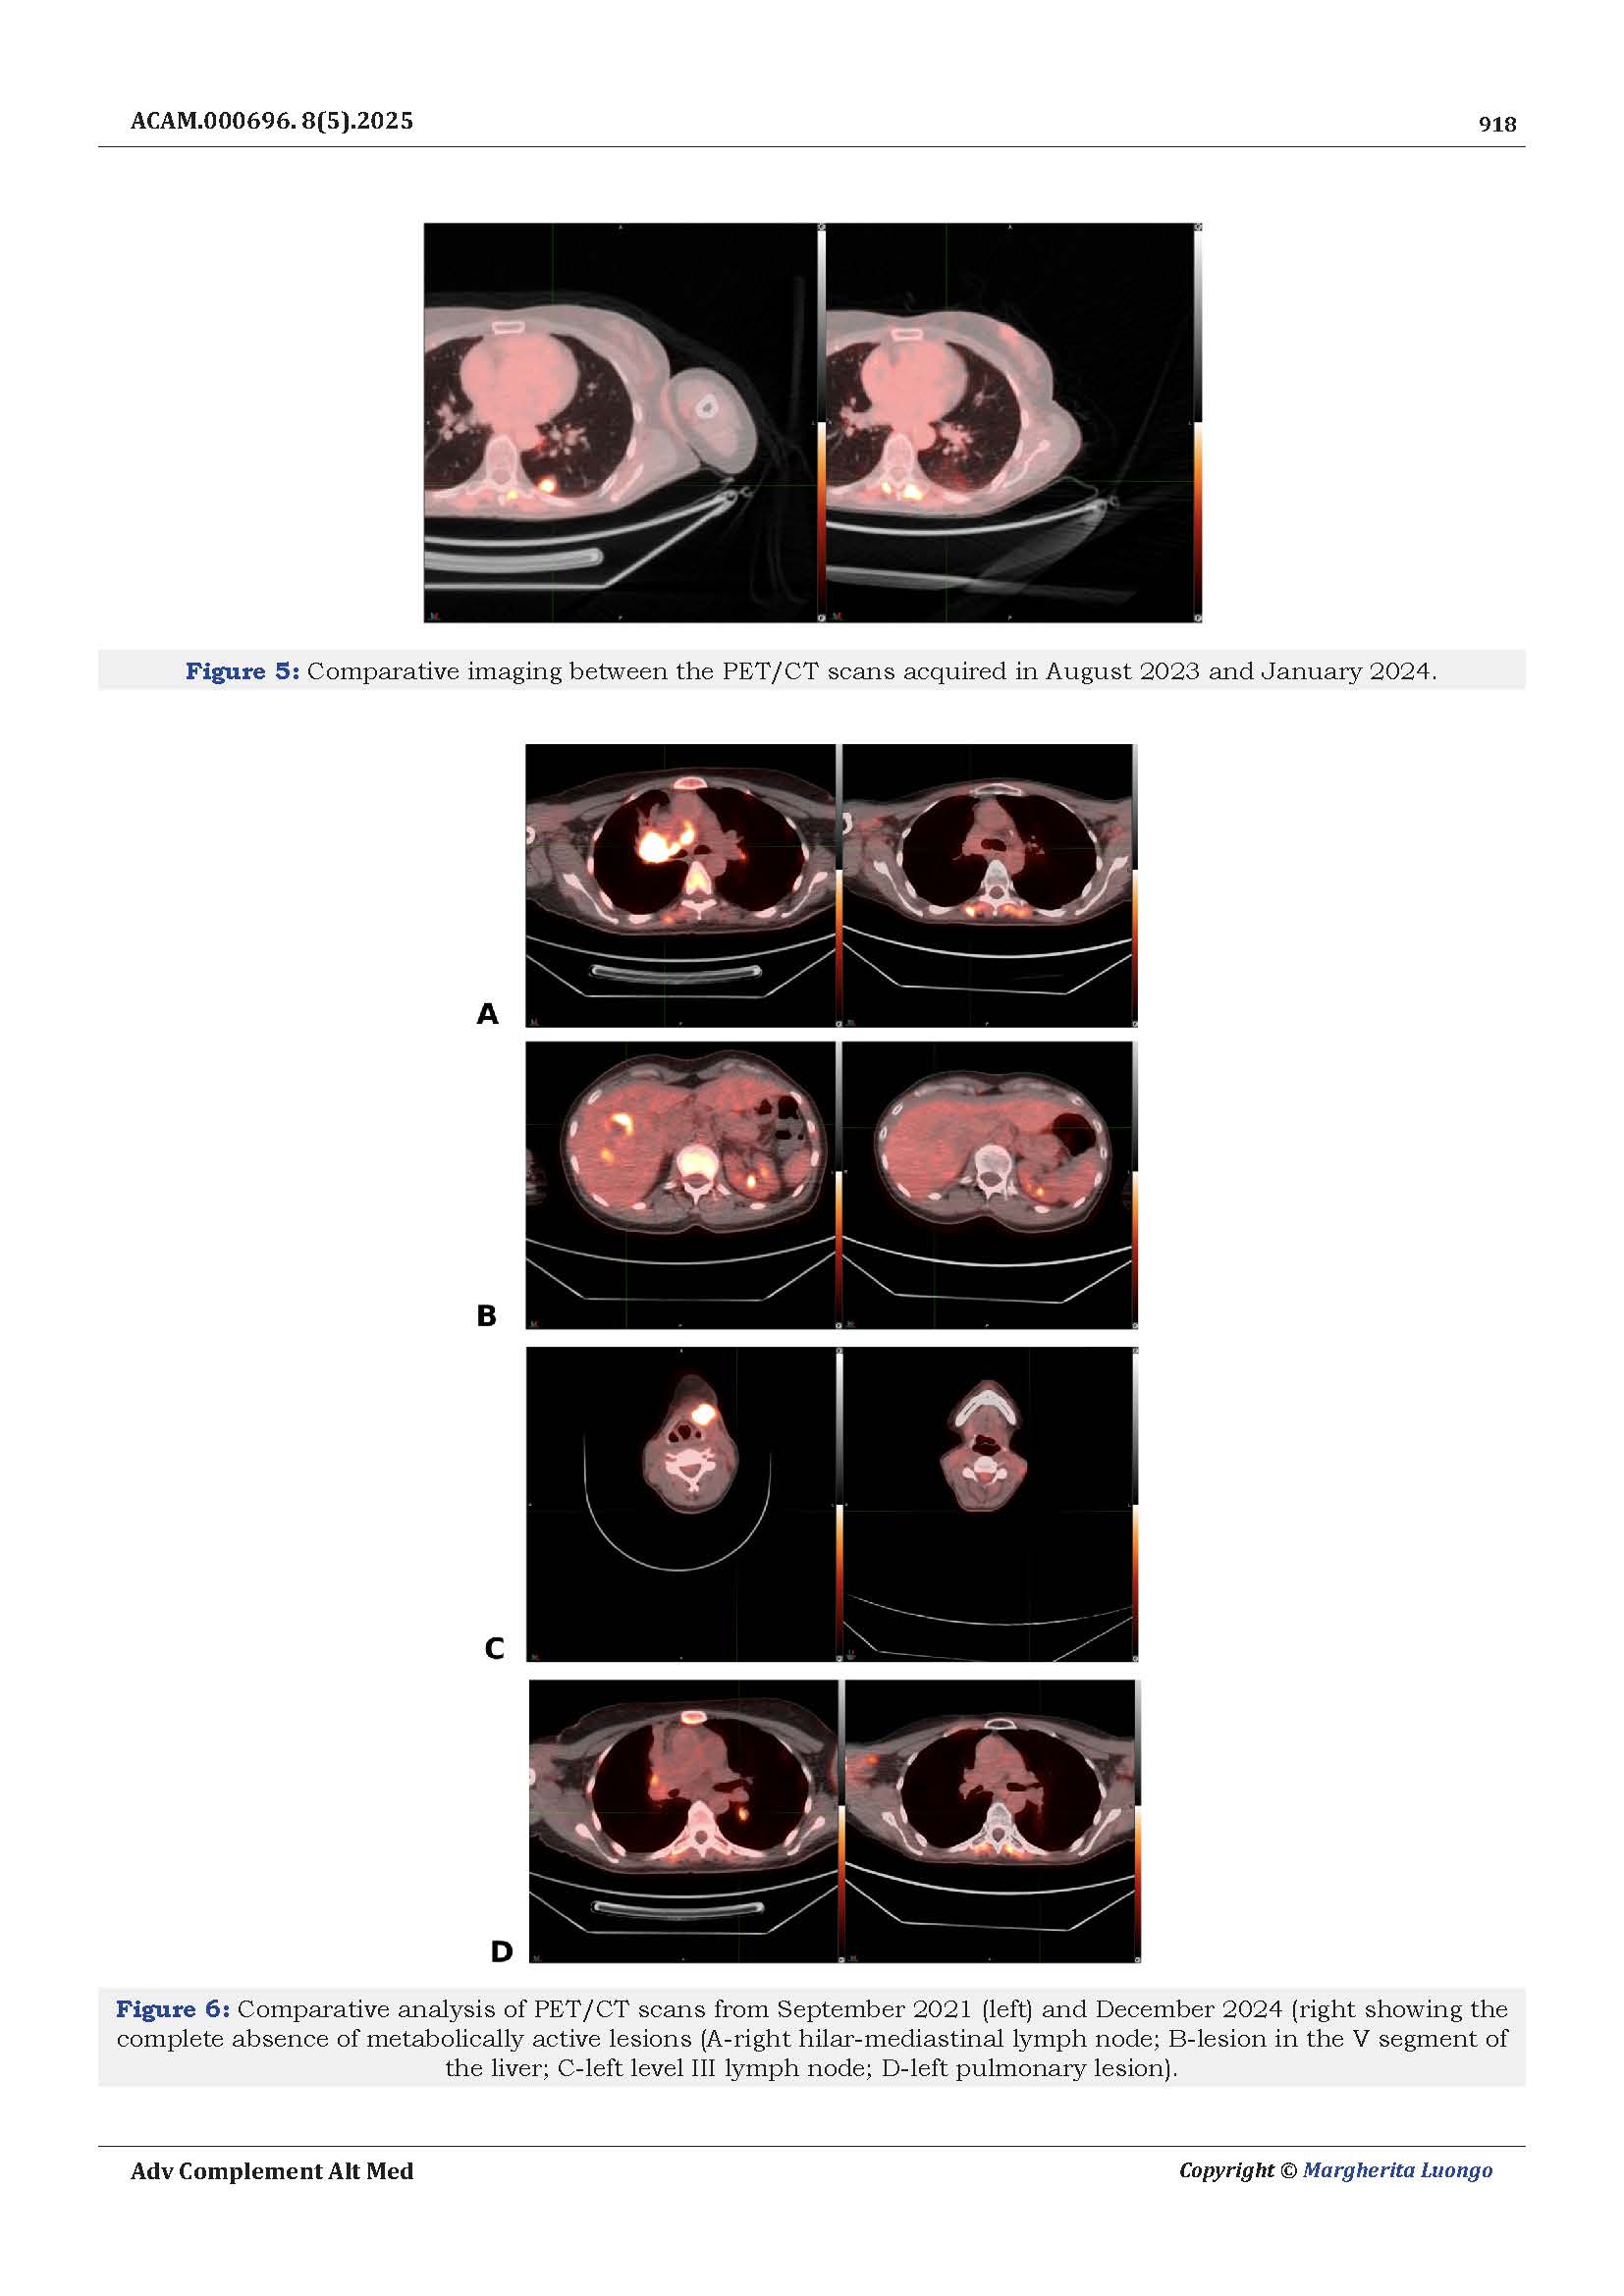

Dopo sei anni di monitoraggi costanti, le risonanze magnetiche hanno mostrato la stabilità della massa tumorale, senza progressione della malattia.

La paziente ha potuto riprendere una vita attiva, mantenendo un buono stato generale e senza gli effetti debilitanti delle terapie più aggressive.

Un risultato importante, che sottolinea come la medicina integrata possa rappresentare un valido supporto anche nei casi più complessi, migliorando la tolleranza alle cure e restituendo benessere globale.